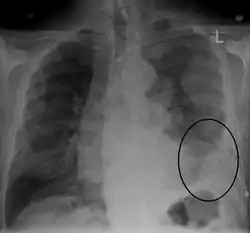

CXR demonstrating a mesothelioma

CT scan showing a left sided mesothelioma with an enlarged mediastinal lymph node